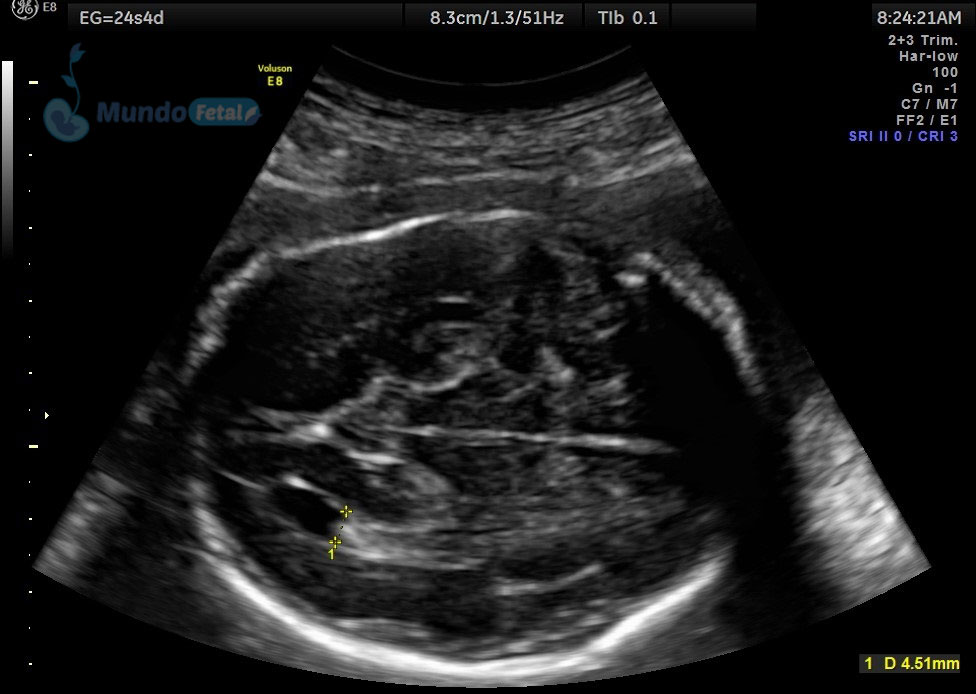

Entre las 18 y 22 semanas, el feto ha desarrollado la mayoría de sus estructuras anatómicas, permitiéndonos valorar de manera detallada todos los órganos del bebe, descartando anomalías anatómicas fetales y datos de cromosomopatías. Prediciendo además preeclampsia (Doppler de arterias uterinas) y parto prematuro (por medio de la medición de la longitud del cérvix). En manos expertas, la detección de anomalías anatómicas supera el 80%.